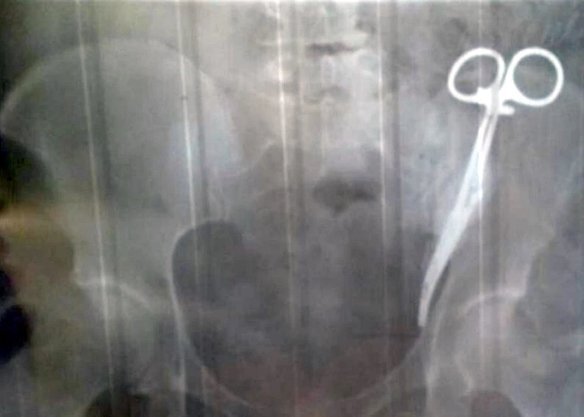

Bác sĩ để quên kéo y tế trong bụng người phụ nữ suốt 23 năm

Người phụ nữ không ngờ thủ phạm gây ra những cơn đau bụng kinh niên của bà suốt nhiều năm qua lại là chiếc kéo y tế bác sĩ để quên trong bụng.